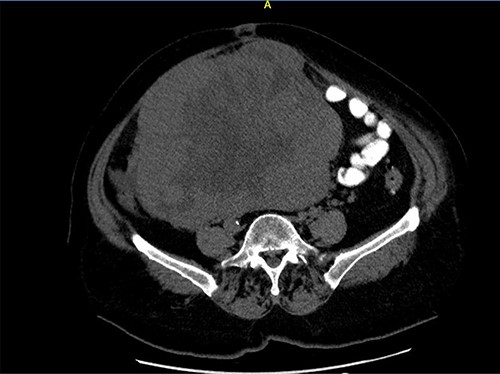

A 68-year-old female patient presented with a palpable abdominal mass in the lower parties of the abdomen. Three months earlier, she noticed painless abdominal distension and frequent urination. She underwent hysterectomy without oophorectomy for treatment of uterine myoma 12 years ago. The results of the transabdominal ultrasound and cross-sectional scan showed a 22 × 21-cm abdominopelvical mass, more right-sided, with both solid and cystic components, and incipient hepatomegaly with single hypodense lesion of liver, 8 mm in diameter. Blood test showed elevated serum cancer antigen 125 (CA 125) 185.9 U/ml, human epididymis secretory protein 4 (HE4) 228.3 pmol/l levels, and the risk of ovarian malignancy algorithm index (Roma index) was high with 79.9%. After a laparotomy, large tumorous mass 22 × 21 cm in diameter was found, which was grayish brown to yellowish color with nodular surface and cystic components, occupying the entire abdominopelvic cavity. (Figs 1 and 2) The tumor was well encapsulated and solid, fixated to the omentum and mesentery with large, nutritional, blood vessels and to surrounding tissue (Figs 3–5). Complete surgical resection of tumor, including bilateral adnexectomy, was performed. The post-operative period was uneventful. After 6 months of follow-up, magnetic resonance imaging of the abdomen and pelvis was performed, and there were no signs of tumor recurrence and serum levels of tumor markers were in reference ranges.

Axial computed tomography (CT) scan shows solid mass in abdominopelvic cavity.